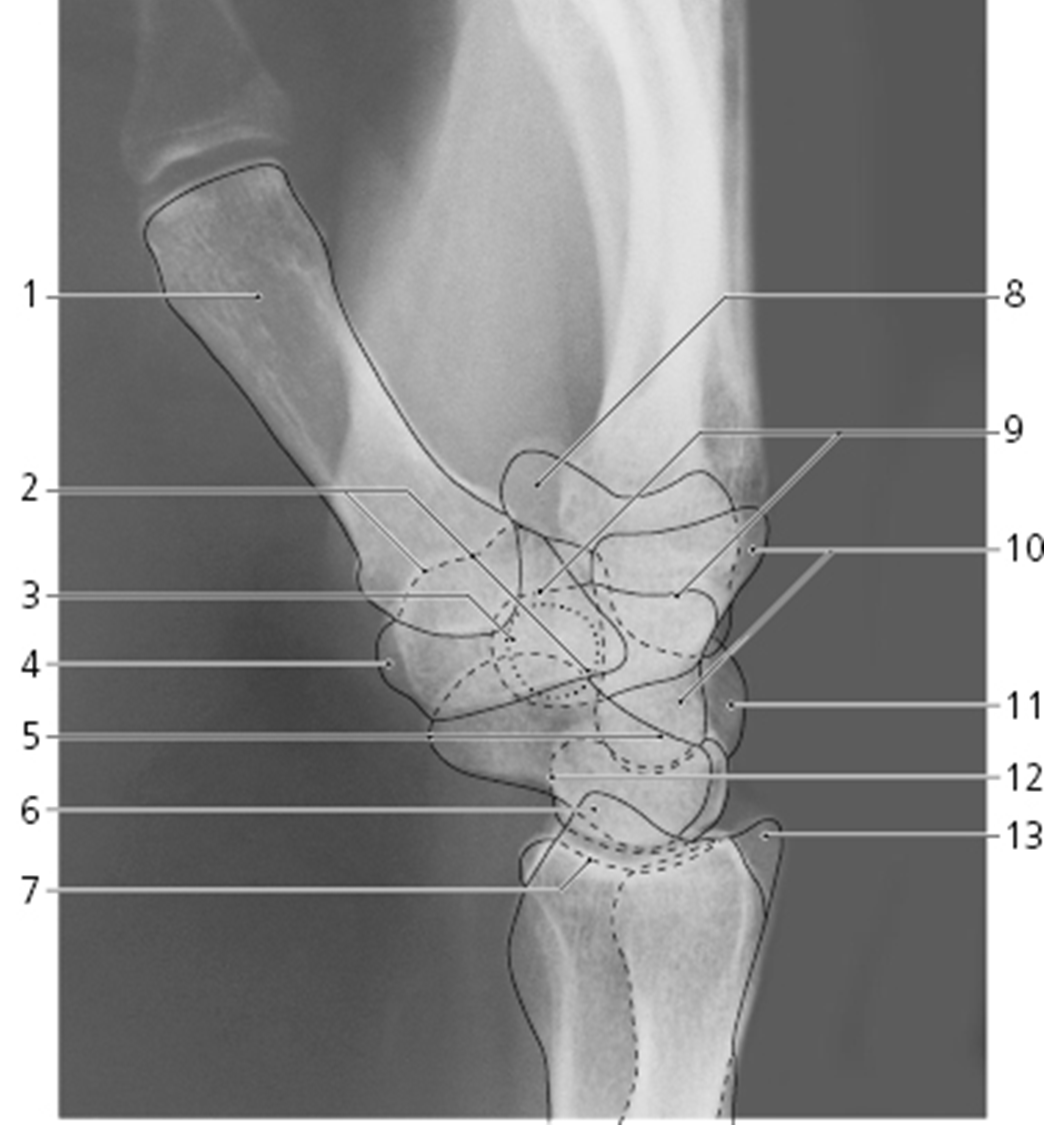

What view is this

oblique wrist

What is 1

1st met

What is 2

scaphoid

What is 3

pisiform

What is 4

triquetrum

What is 5

What is 6

What is 7

What is 8

What is 9

What is 10

What is 11

What is 12

What is 13